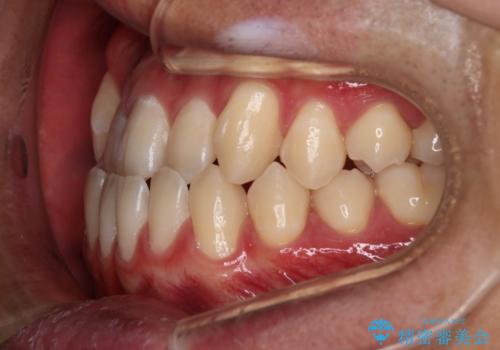

【審美装置】前歯の反対咬合改善

- 前歯の歯並びと噛み合わせを主訴に来院されました。

左右の噛み合わせが反対咬合であることと下顎の皮質骨が薄いため治療計画をしっかりと立てて行う必要のあるケースでした。